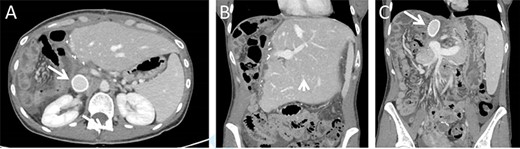

The immediate postoperative course was uneventful and the patient was discharged in good condition nine days following surgery. Twelve days after discharge the patient was readmitted due complaints of abdominal pain. Her vital signs, physical examination and laboratory blood indices were normal. A CT scan revealed a small amount of fluid in the abdominal cavity and thrombophlebitis of the left external iliac vein (Probably triggered by the cannula placed for venous–venous bypass). The remnant liver was markedly hypertrophied and the IVC Gore-tex graft was patent (Fig. 3).

Postoperative CT imaging. (A) Axial CT image depicting patent IVC graft (arrow). (B + C) Coronal images depicting hypertrophied remnant liver (arrowhead), patent portal vein and IVC graft (arrow).